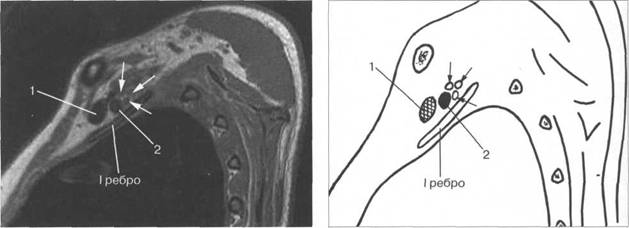

T2-BH(FATSAT).

I располагается позади. Иногда удается хорошо различить ин 10510f510k дивидуальное деление пучков. Ла-